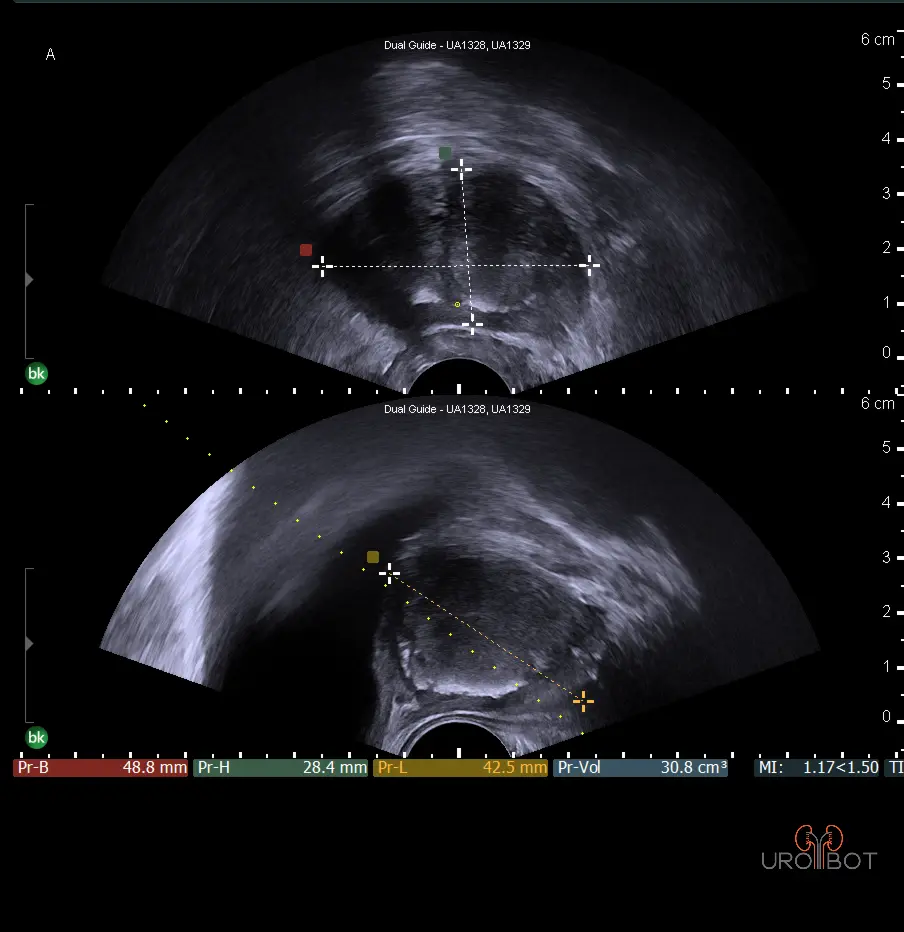

Es handelt sich bei dieser Untersuchung um eine Ultraschalluntersuchung der Prostata. Dafür wird ein stabförmiger Ultraschallkopf in den Enddarm des Patienten eingeführt. Die Untersuchung kann in Seitenlage oder in Steinschnittlage durchgeführt werden. Mit der speziellen Ultraschallsonde kann die Prostata gleichzeitig längst und quer dargestellt werden. Beurteilt werden:

- Form,

- Größe,

- Abgrenzbarkeit,

- die verschiedenen Zonen der Prostata,

- Homogenität,

- Samenblasen.

Das Video zeigt eine sonographische Untersuchung der Prostata, durchgeführt über eine sogenannte transrektale Ultraschallsonde.